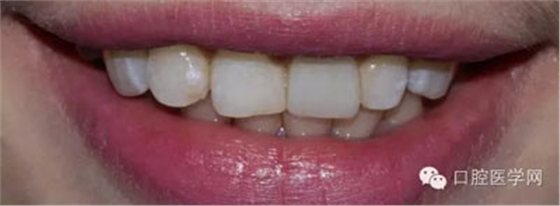

患者:女,大學(xué)生

主訴:左上門牙不好看,要求重做

現(xiàn)病史:五年前因左上門牙有扭轉(zhuǎn)不好看,有到外院做烤瓷牙,于近兩三年該牙較經(jīng)常出現(xiàn)牙齦紅腫和流血,且該牙牙齦有輕微發(fā)黑,患者還覺得該牙的顏色及形態(tài)不好看,要求重新做